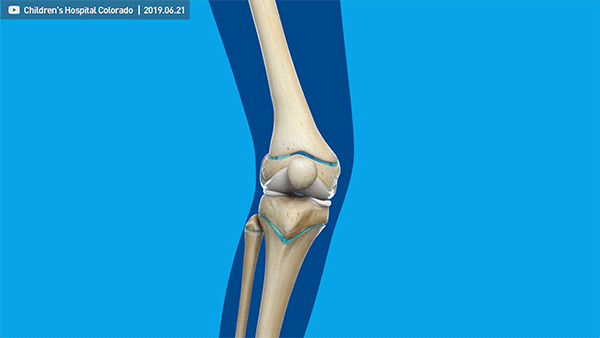

这个角度一般用胫股角来衡量,也就是大腿和小腿的轴线在膝关节处的夹角,其数值随年龄发生特征性变化。

你的膝关节内侧承受着 70% 的重量,随着年龄增长,肌肉力量下降,膝关节受力不均衡,极易引发退行性膝关节骨性关节炎。长此以往,膝关节内侧软骨平面总受磨损,造成膝内翻畸形。